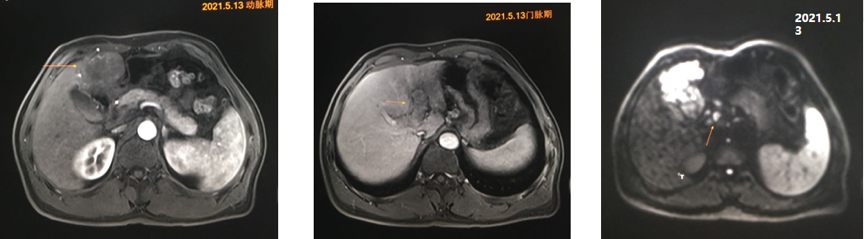

腹部普美显增强MRI:肝顶及肝左叶(S2-4)多发结节及团块,考虑肝癌,门静脉左支癌栓形成,腹膜后多发小结节,转移待除外,肝硬化,肝多发再生结节(图1)。

图1.2021年5月13日MRI